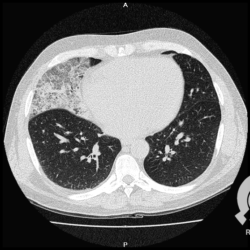

Os agentes etiológicos infecciosos são variados (bactérias, vírus, fungos, parasitas…), mas o que ocorre nos pulmões durante uma infecção por qualquer tipo de agente é a substituição do ar alveolar por secreção (pus, muco, eventualmente sangue ou necrose…) e com isso a manifestação radiográfica vai ser a mesma já que todas estas secreções apresentam a mesma densidade radiográfica: partes moles.

E o nome dado a esta alteração radiográfica que corresponde à substituição do ar alveolar por líquido é a consolidação alveolar.

Uma consolidação alveolar é, por definição, uma opacidade (imagem densa, branquinha) homogênea ou às vezes heterogênea (pela presença de calcificações ou cavidades), de limites mal definidos, exceto quando toca a pleura da parede ou das cissuras pulmonares. É um termo usado tanto em radiografia, como em tomografia computadorizada. Na tomografia, um outro termo é usado: vidro fosco, que é uma opacidade (branquinha mas não tanto como a consolidação), que borra o pulmão mas deixa ver os vasos de permeio (igual bigode de adolescente: dá pra ver todo o fundo).

Nós vamos mostrar aqui um pequeno apanhado de pneumonias de variados agentes, em diversos segmentos e lobos pulmonares, com extensões variadas. O objetivo é identificar o padrão radiológico de consolidação alveolar e não determinar o agente infeccioso, isso vai ser assunto para mais adiante. Aliás já antecipo que é fundamental saber localizar a lesão, porque alguns destes bichos gostam de determinados segmentos, alguns tumores também têm as suas preferências, então localização é fundamental. Se localização não fosse importante, um apartamento na beira do mar sairia o mesmo preço de um apartamento de frente pra BR-101, concordam?